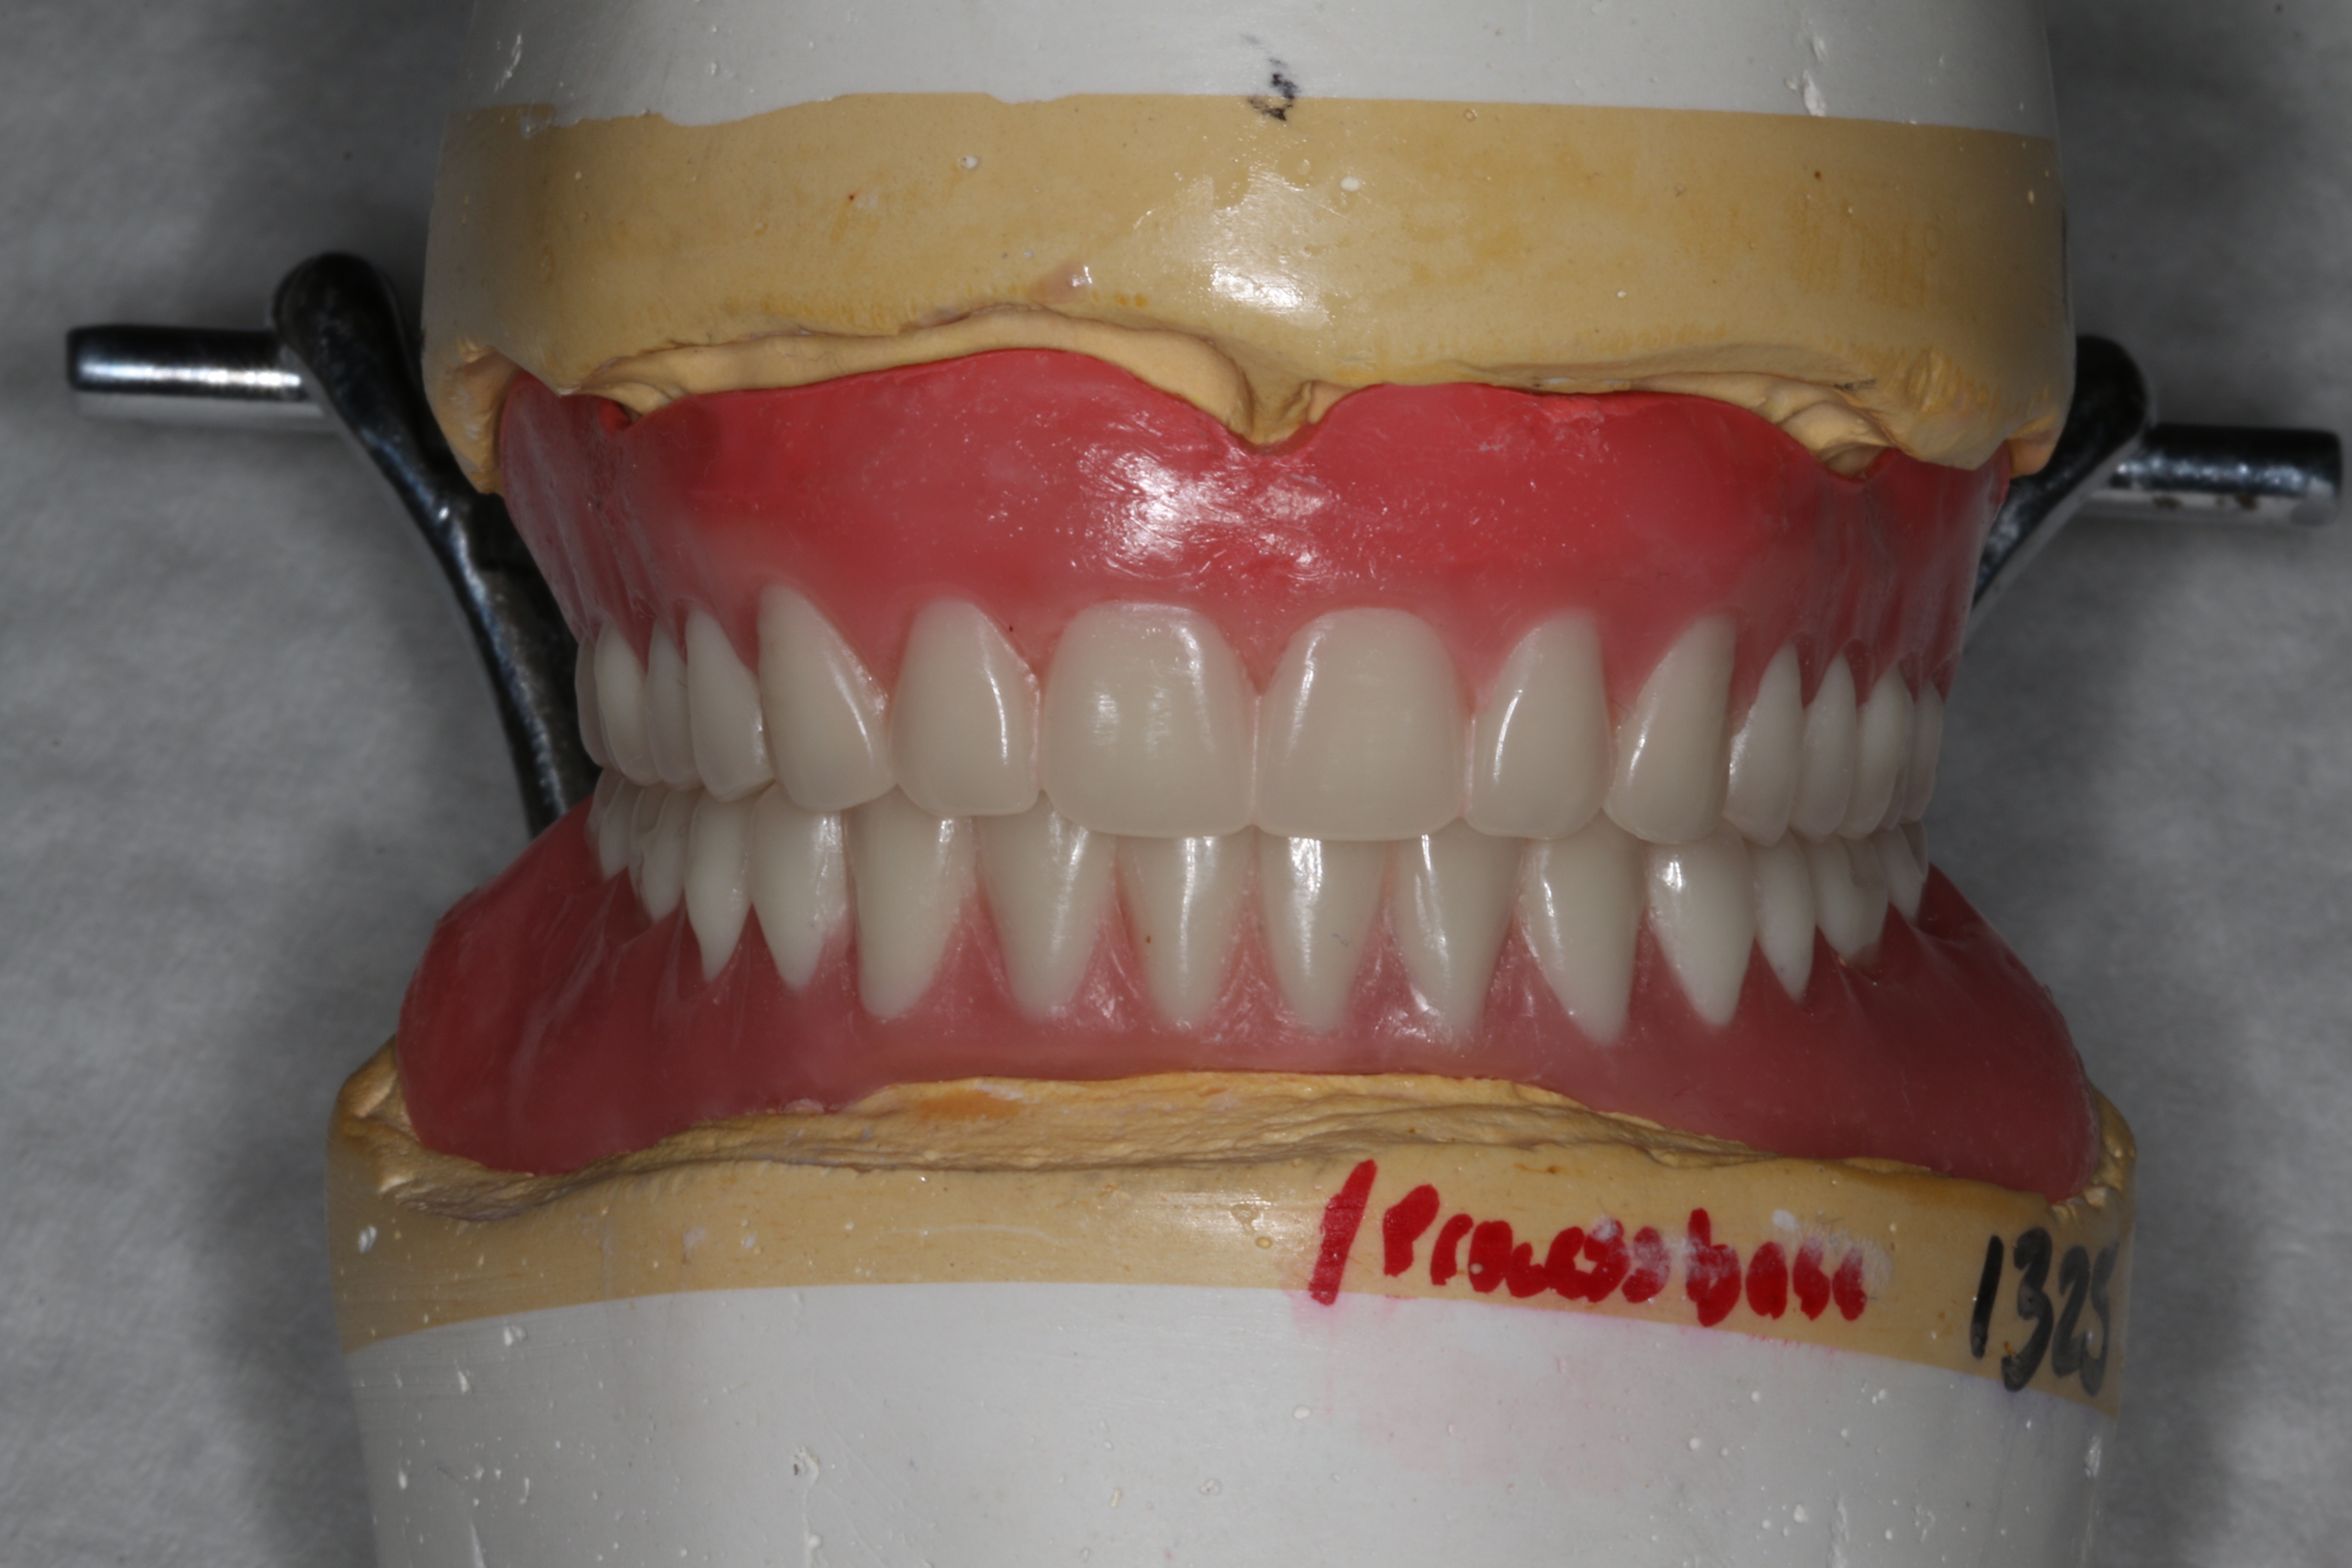

Fig 13. Final set-up approved by the patient.

Figure 13